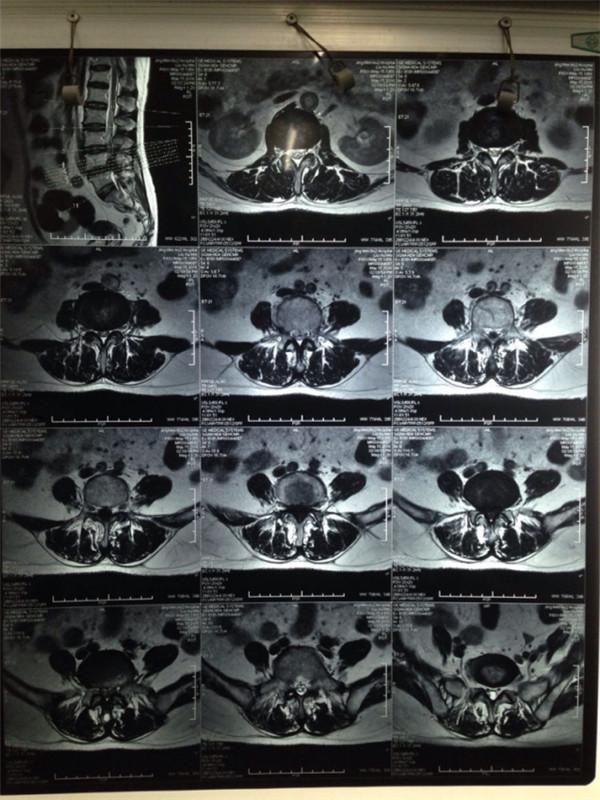

腰椎间盘突出症患者MRI显示~